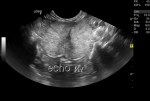

Ultrasound

Ultrasonography is the best method, safe and accurate. It allows the assessment of pregnancy status, and viability of the fetuses.

Gestational sacs are visible as early as day 18-20 after LH peak, but its recommend to examine not before day 21-25 because the small fluid-filled structures may be obscured by intestinal gas earlier.

Fetal heartbeat can be detected from days 16-25 in the queen and from days 23-28 in the bitch. Fetal heart rate should be more than 200 beats per minute as decreasing rate indicates fetal stress. Several ultrasound methods can be used to calculate it.

In contrary with what is believed, ultrasonography is NOT the method of choice for assessment of litter size. Counting number of fetuses is difficult, especially in large litters.

Canine fetus, day 39